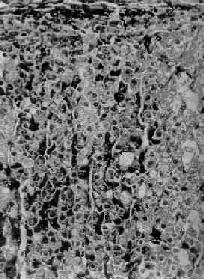

图15-14 肾上腺皮质弥漫增生

图15-13之镜下观,肾上腺皮质束状带弥漫性增厚